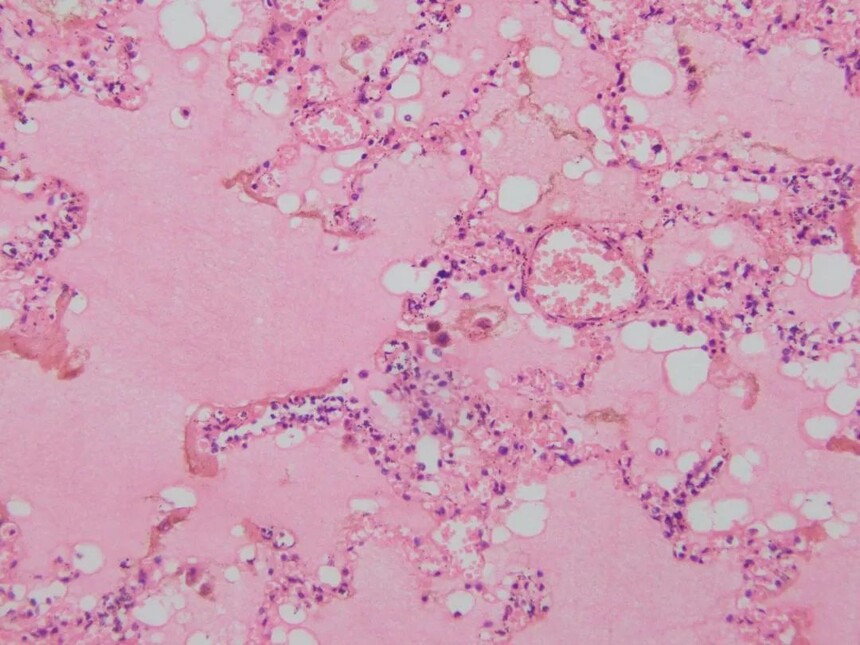

3、急性肺水肿

肺泡壁毛细血管扩张充血,肺泡腔内含水肿液。

4、慢性肺淤血

肺组织切片可见肺泡间隔明显增宽,肺泡壁毛细血管普遍扩张充血。其横断面镜下可见多个红细胞;大多数肺泡腔内充满粉红色液体(水肿液)和少量红细胞,并可见少量气体空泡。